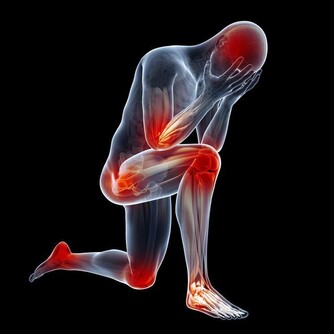

現代醫學又研究證明,生氣不僅會帶來強烈的生理變化,而且其產生的激素比任何情緒都複雜,且具有毒性。到底生氣後,身體8大器官會發生什麼變化?今天就隨著營養師看看吧。

研究發現,健康的愛發脾氣者罹患心髒病而死亡的機率高出19%。生氣時,心臟的收縮力加強,心跳加速,大量的血液湧向心臟,心臟則需要加倍工作。這時就會出現心率不齊、心肌缺血、胸悶、心慌,甚至誘發心絞痛和心肌梗塞。

俗話說怒傷肝,這句話一點也不假。情緒與“肝火”關係極為密切,不良的情緒刺激會導致肝臟損害,而肝臟損害又會加重情緒失衡。生氣時,人體會分泌一種叫“兒茶酚胺”的物質,作用於中樞神經系統,使血糖升高,脂肪酸分解加強,血液和肝細胞內的毒素相應增加。

生氣時胃部血流量減少,供血量不足,胃腸蠕動困難,食慾不振,引起腸胃功能紊亂、胃潰瘍等。

生氣易引起吸就會急促,甚至出現過度換氣的現象,肺泡不停擴張,得不到放鬆,沒時間收縮,

也就得不到應有的放鬆和休息,從而危害肺的健康,嚴重時會引發哮喘等病症。

5、腎

生氣時腎血管收縮、缺血、腎小管重吸收功能紊亂、腎小球濾過功能差,

就會出現口渴、多尿、尿頻、尿急、尿失禁等,

嚴重時會使尿糖、尿蛋白增加或出現貧血、腎虛、腎功能衰竭。

中醫講:“腎主骨,骨升髓”,生氣多時會導致骨痛,肢體麻木,關節炎等。